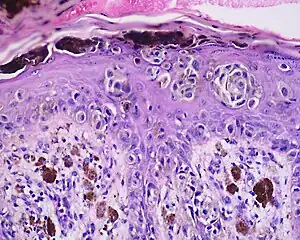

Histology

The main characteristic of acral lentiginous melanoma is continuous proliferation of atypical melanocytes at the dermoepidermal junction.[17] Other histological signs of acral lentiginous melanoma include dermal invasion and desmoplasia.[18]

According to Scolyer et al.,[19] ALM "is usually characterized in its earliest recognisable form as single atypical melanocytes scattered along the junctional epidermal layer".